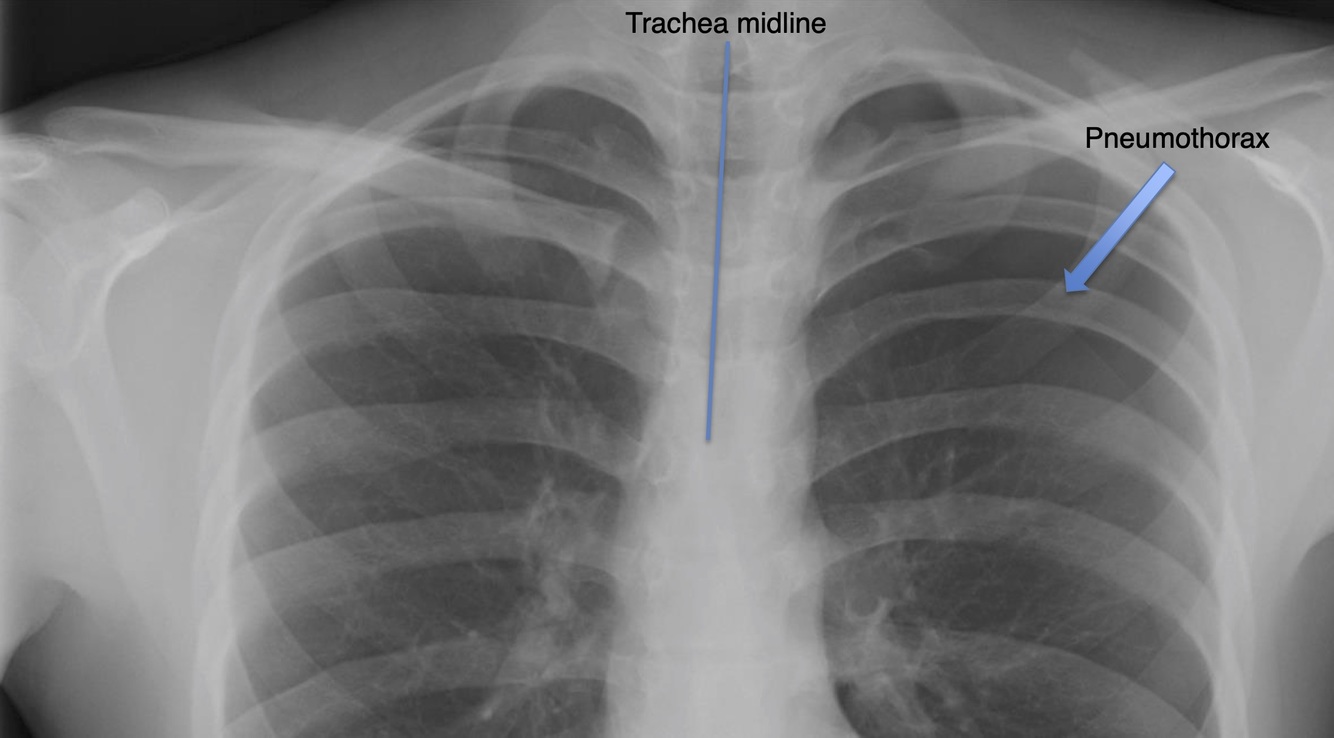

Trachea

Normally found in the midline.

Abnormalities:

Pneumothorax

Air trapped within the pleural cavity.